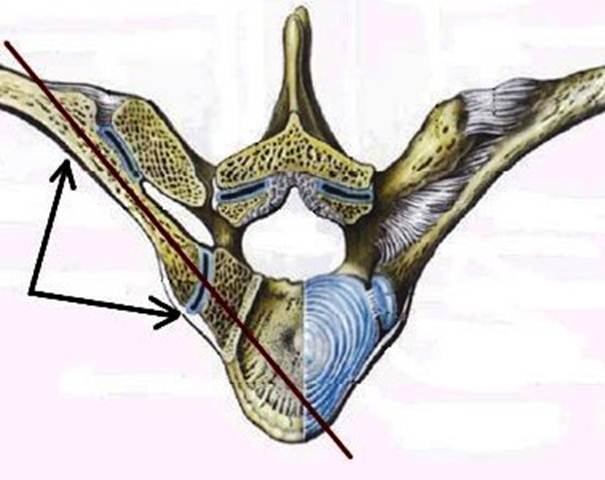

S: Стрелка указывает на art. Costotransversaria

S: Стрелка указывает на art. Capitis costae

S: Стрелками выделен art…